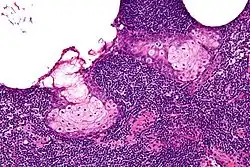

| High magnification micrograph of a sebaceous lymphadenoma. H&E stain. | |